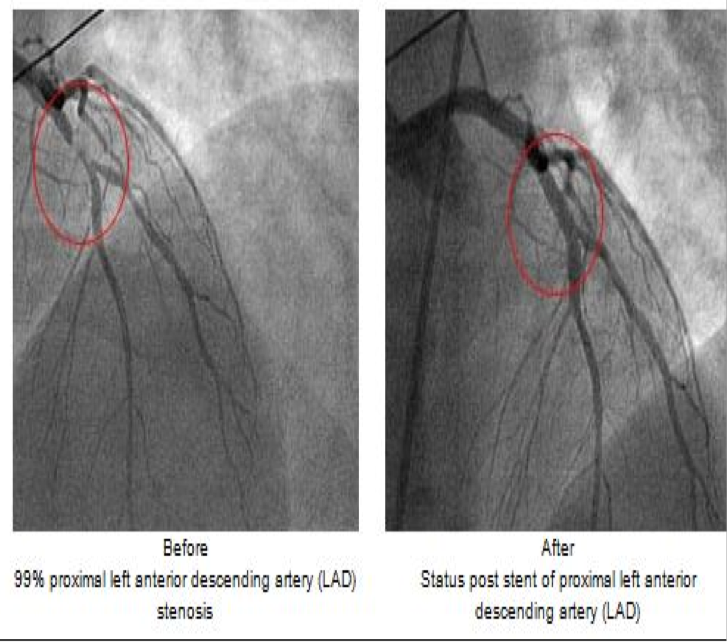

Cardiac catheterization (dilate BV, make sure no blockage)

Cardiac catheterization

Fluoroscopy used as an adjunct to see the flow of blood through the coronary arteries in order to evaluate the presence of arterial blockages